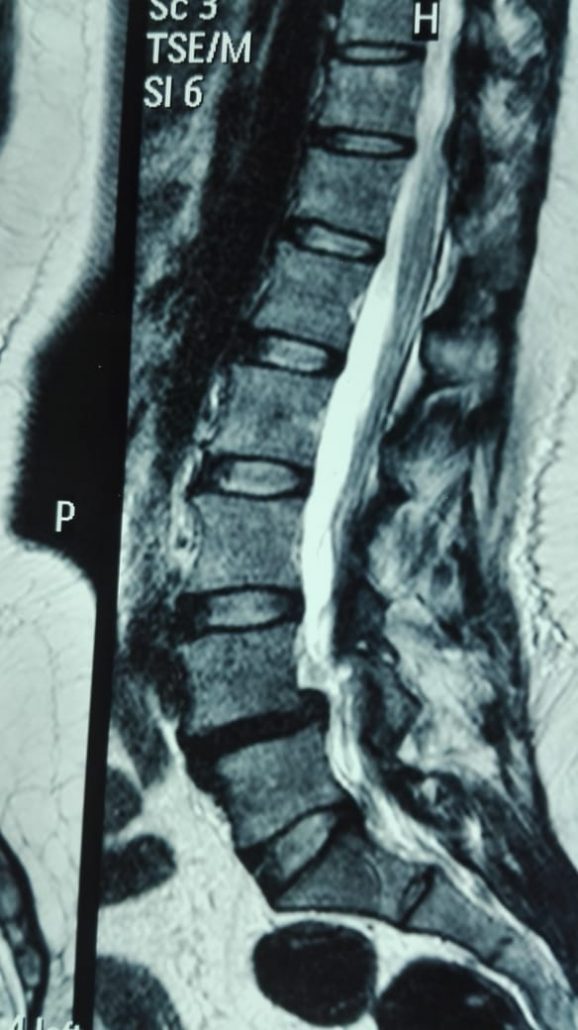

Latest Spine Fixation Technique